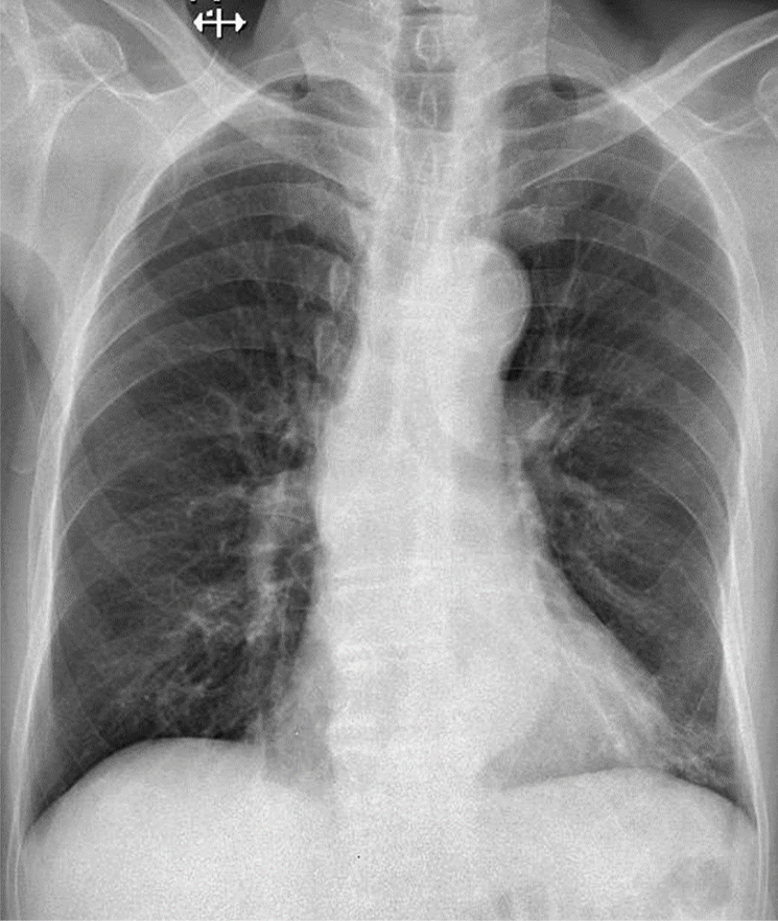

1-Xơ thùy dưới phổi (T) 2-Cung động mạch chủ đóng vôi 3-Vẹo cột sống ngực sang (P)